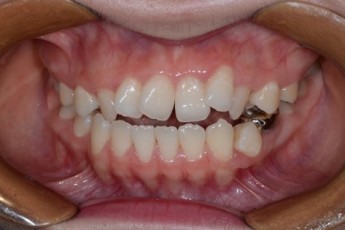

Before

After